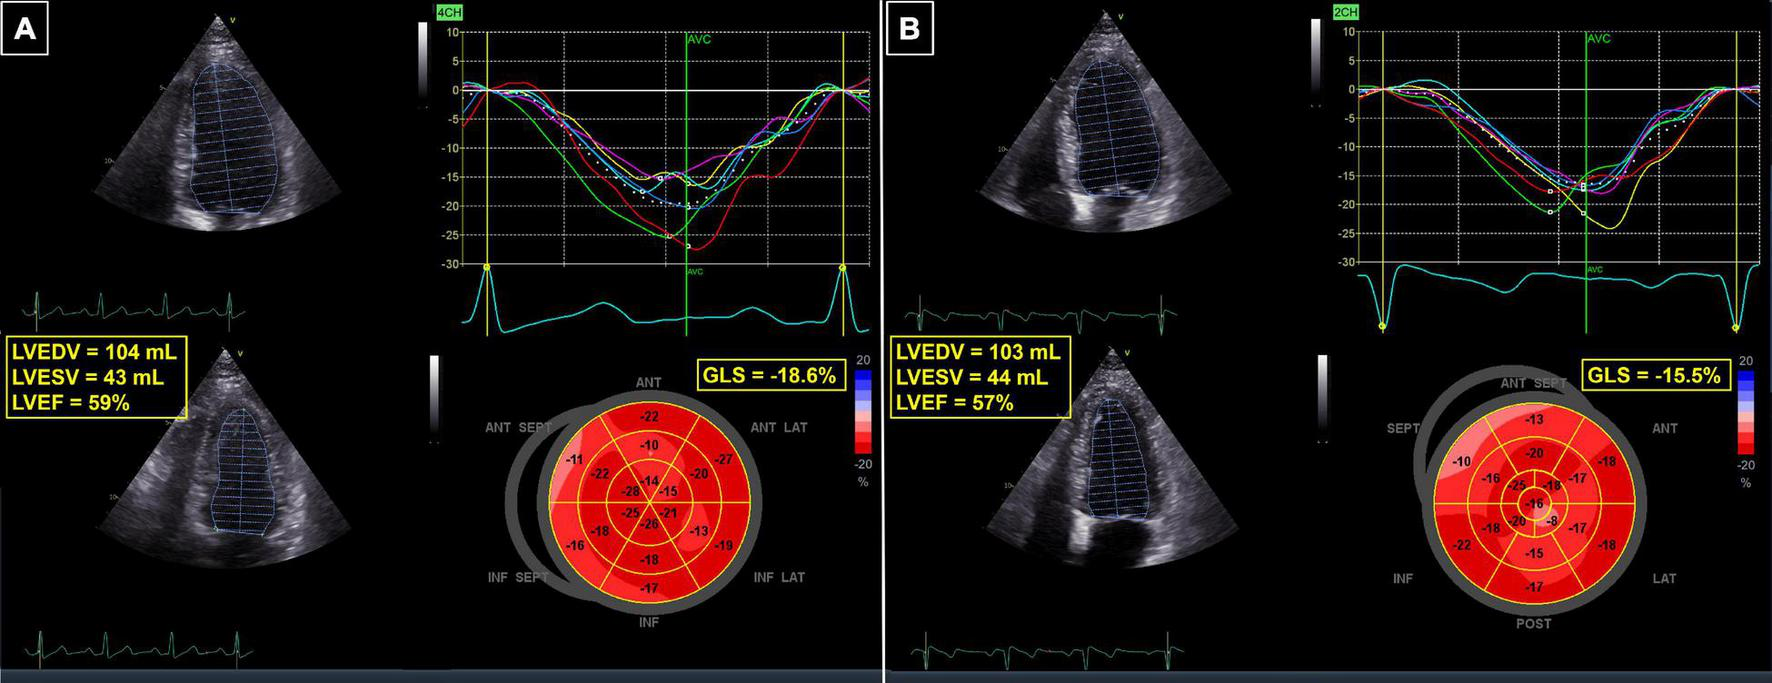

FIGURE 3

62-year-old patient with breast cancer undergoing chemotherapy with anthracyclines and radiotherapy. (A) Baseline echocardiogram, showing normal LVEF and GLS. (B) Follow-up echocardiogram 3 months after completion of therapy—the LVEF was still normal, but a 17% relative reduction in GLS revealed cardiotoxicity. GLS, global longitudinal strain; LVEDV, left ventricular end-diastolic volume; LVEF, left ventricular ejection fraction; LVESV, left ventricular end-systolic volume.